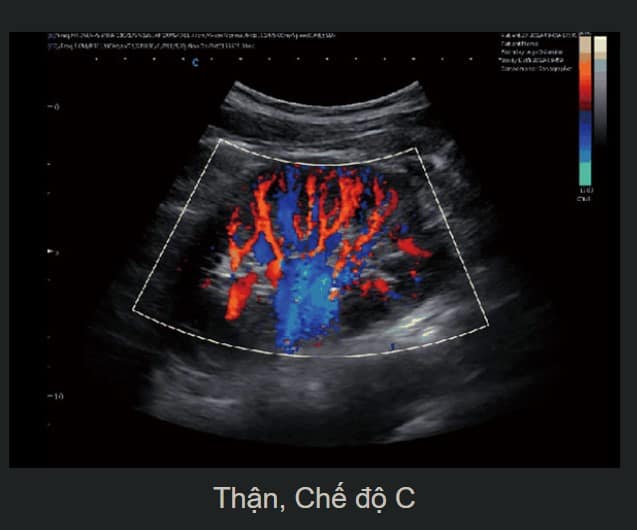

Doppler Thông Minh

Tính năng này tự động điều chỉnh hướng ROI, PFR ở chế độ màu, tạo ra các hình ảnh Doppler sắc nét và dễ đọc.

Hình Ảnh Toàn Cảnh Màu

Máy cho phép phóng to vùng quét trong thời gian thực, cung cấp thông tin chi tiết về màu sắc và cấu trúc mạch máu.